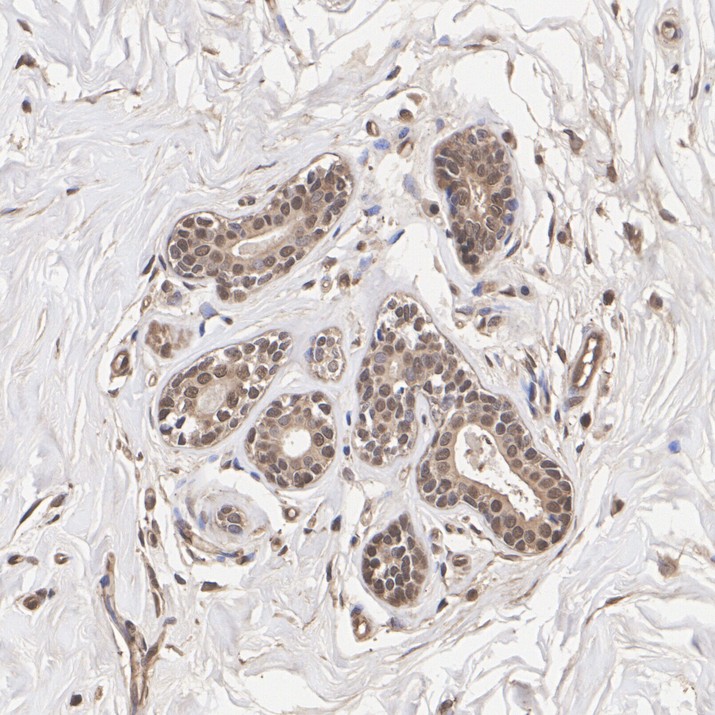

Immunohistochemical analysis of paraffin-embedded human breast cancer tissue with Rabbit anti-LDHA antibody (HA723547) at 1/20,000 dilution.

The section was pre-treated using heat mediated antigen retrieval with Tris-EDTA buffer (pH 9.0) for 20 minutes. The tissues were blocked in 1% BSA for 20 minutes at room temperature, washed with ddH2O and PBS, and then probed with the primary antibody (HA723547) at 1/20,000 dilution for 1 hour at room temperature. The detection was performed using an HRP conjugated compact polymer system. DAB was used as the chromogen. Tissues were counterstained with hematoxylin and mounted with DPX.